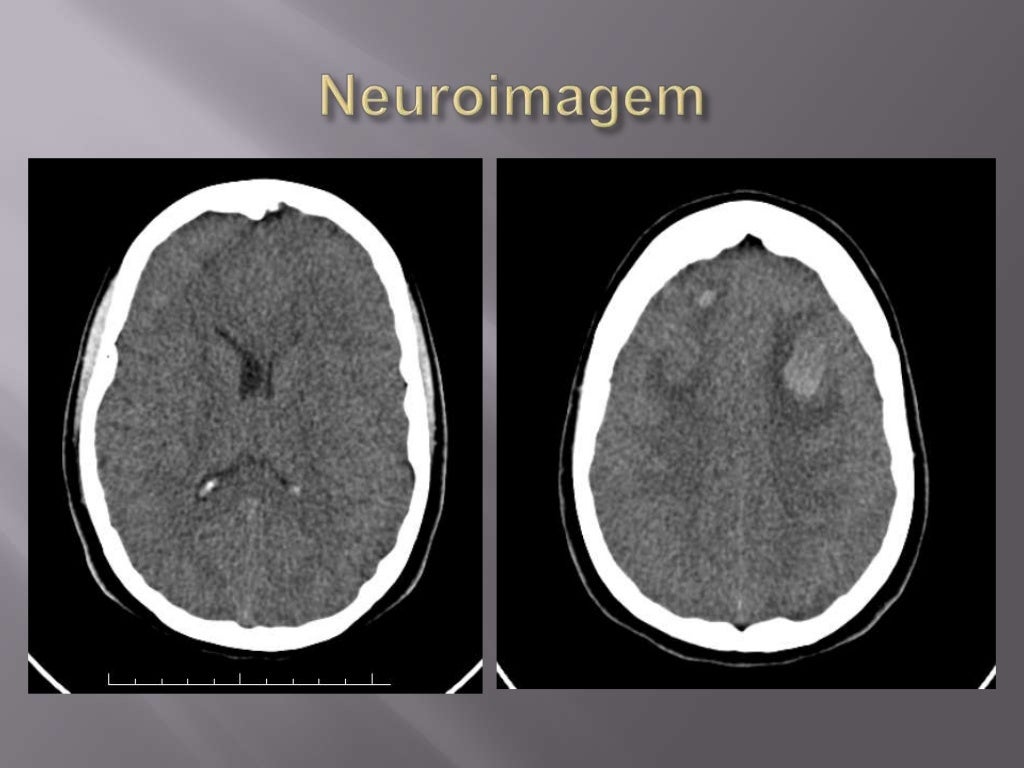

Dor de cabeça. A cefaleia (dor de cabeça) é o sintoma mais frequente da trombose venosa cerebral, estando presente em cerca de 90% dos pacientes. A dor de cabeça é geralmente o primeiro sintoma da TVC e pode ser o único em alguns casos. A cefaleia também pode preceder outros sintomas e sinais por dias ou até semanas.. A trombose venosa cerebral é um evento que ocorre dentro de uma das veias que drenam o sangue do cérebro de volta para o coração. Diferentes fatores podem desregular o funcionamento normal do organismo e fazer com que o sangue forme um coágulo. É o que se chama em medicina de "trombo". Essa partícula de sangue endurecido pode entupir.